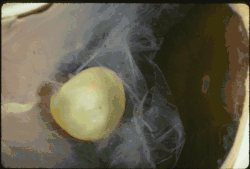

| Ectopia lentis in Marfan syndrome: Zonular fibers are seen. | |

In Marfan syndrome, the health of the eye can be affected in many ways, but the principal change is partial lens dislocation, where the lens is shifted out of its normal position.[17] This occurs because of weakness in the ciliary zonules, the connective tissue strands which suspend the lens within the eye. The mutations responsible for Marfan syndrome weaken the zonules and cause them to stretch. The inferior zonules are most frequently stretched resulting in the lens shifting upwards and outwards, but it can shift in other directions as well. Nearsightedness (myopia), and blurred vision are common due to connective tissue defects in the eye.[18] Farsightedness can also result particularly if the lens is highly subluxated. Subluxation (partial dislocation) of the lens can be detected clinically in about 60% of people with Marfan syndrome by the use of a slit-lamp biomicroscope.[18] If the lens subluxation is subtle, then imaging with high-resolution ultrasound biomicroscopy might be used.[19]